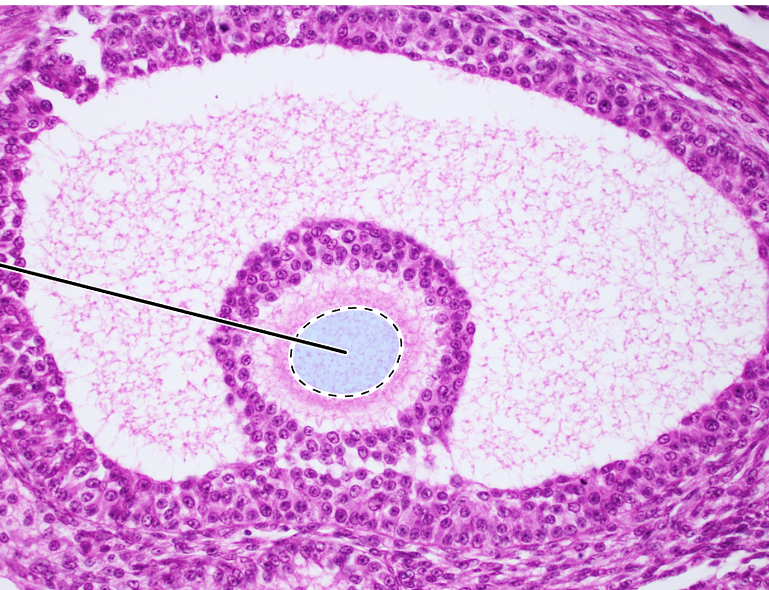

ovary (tertiary follicle)

oocyte

zona pellucida

granulosa cells

antra

theca interna

ovary (mature tertiary follicle)

corona radiata